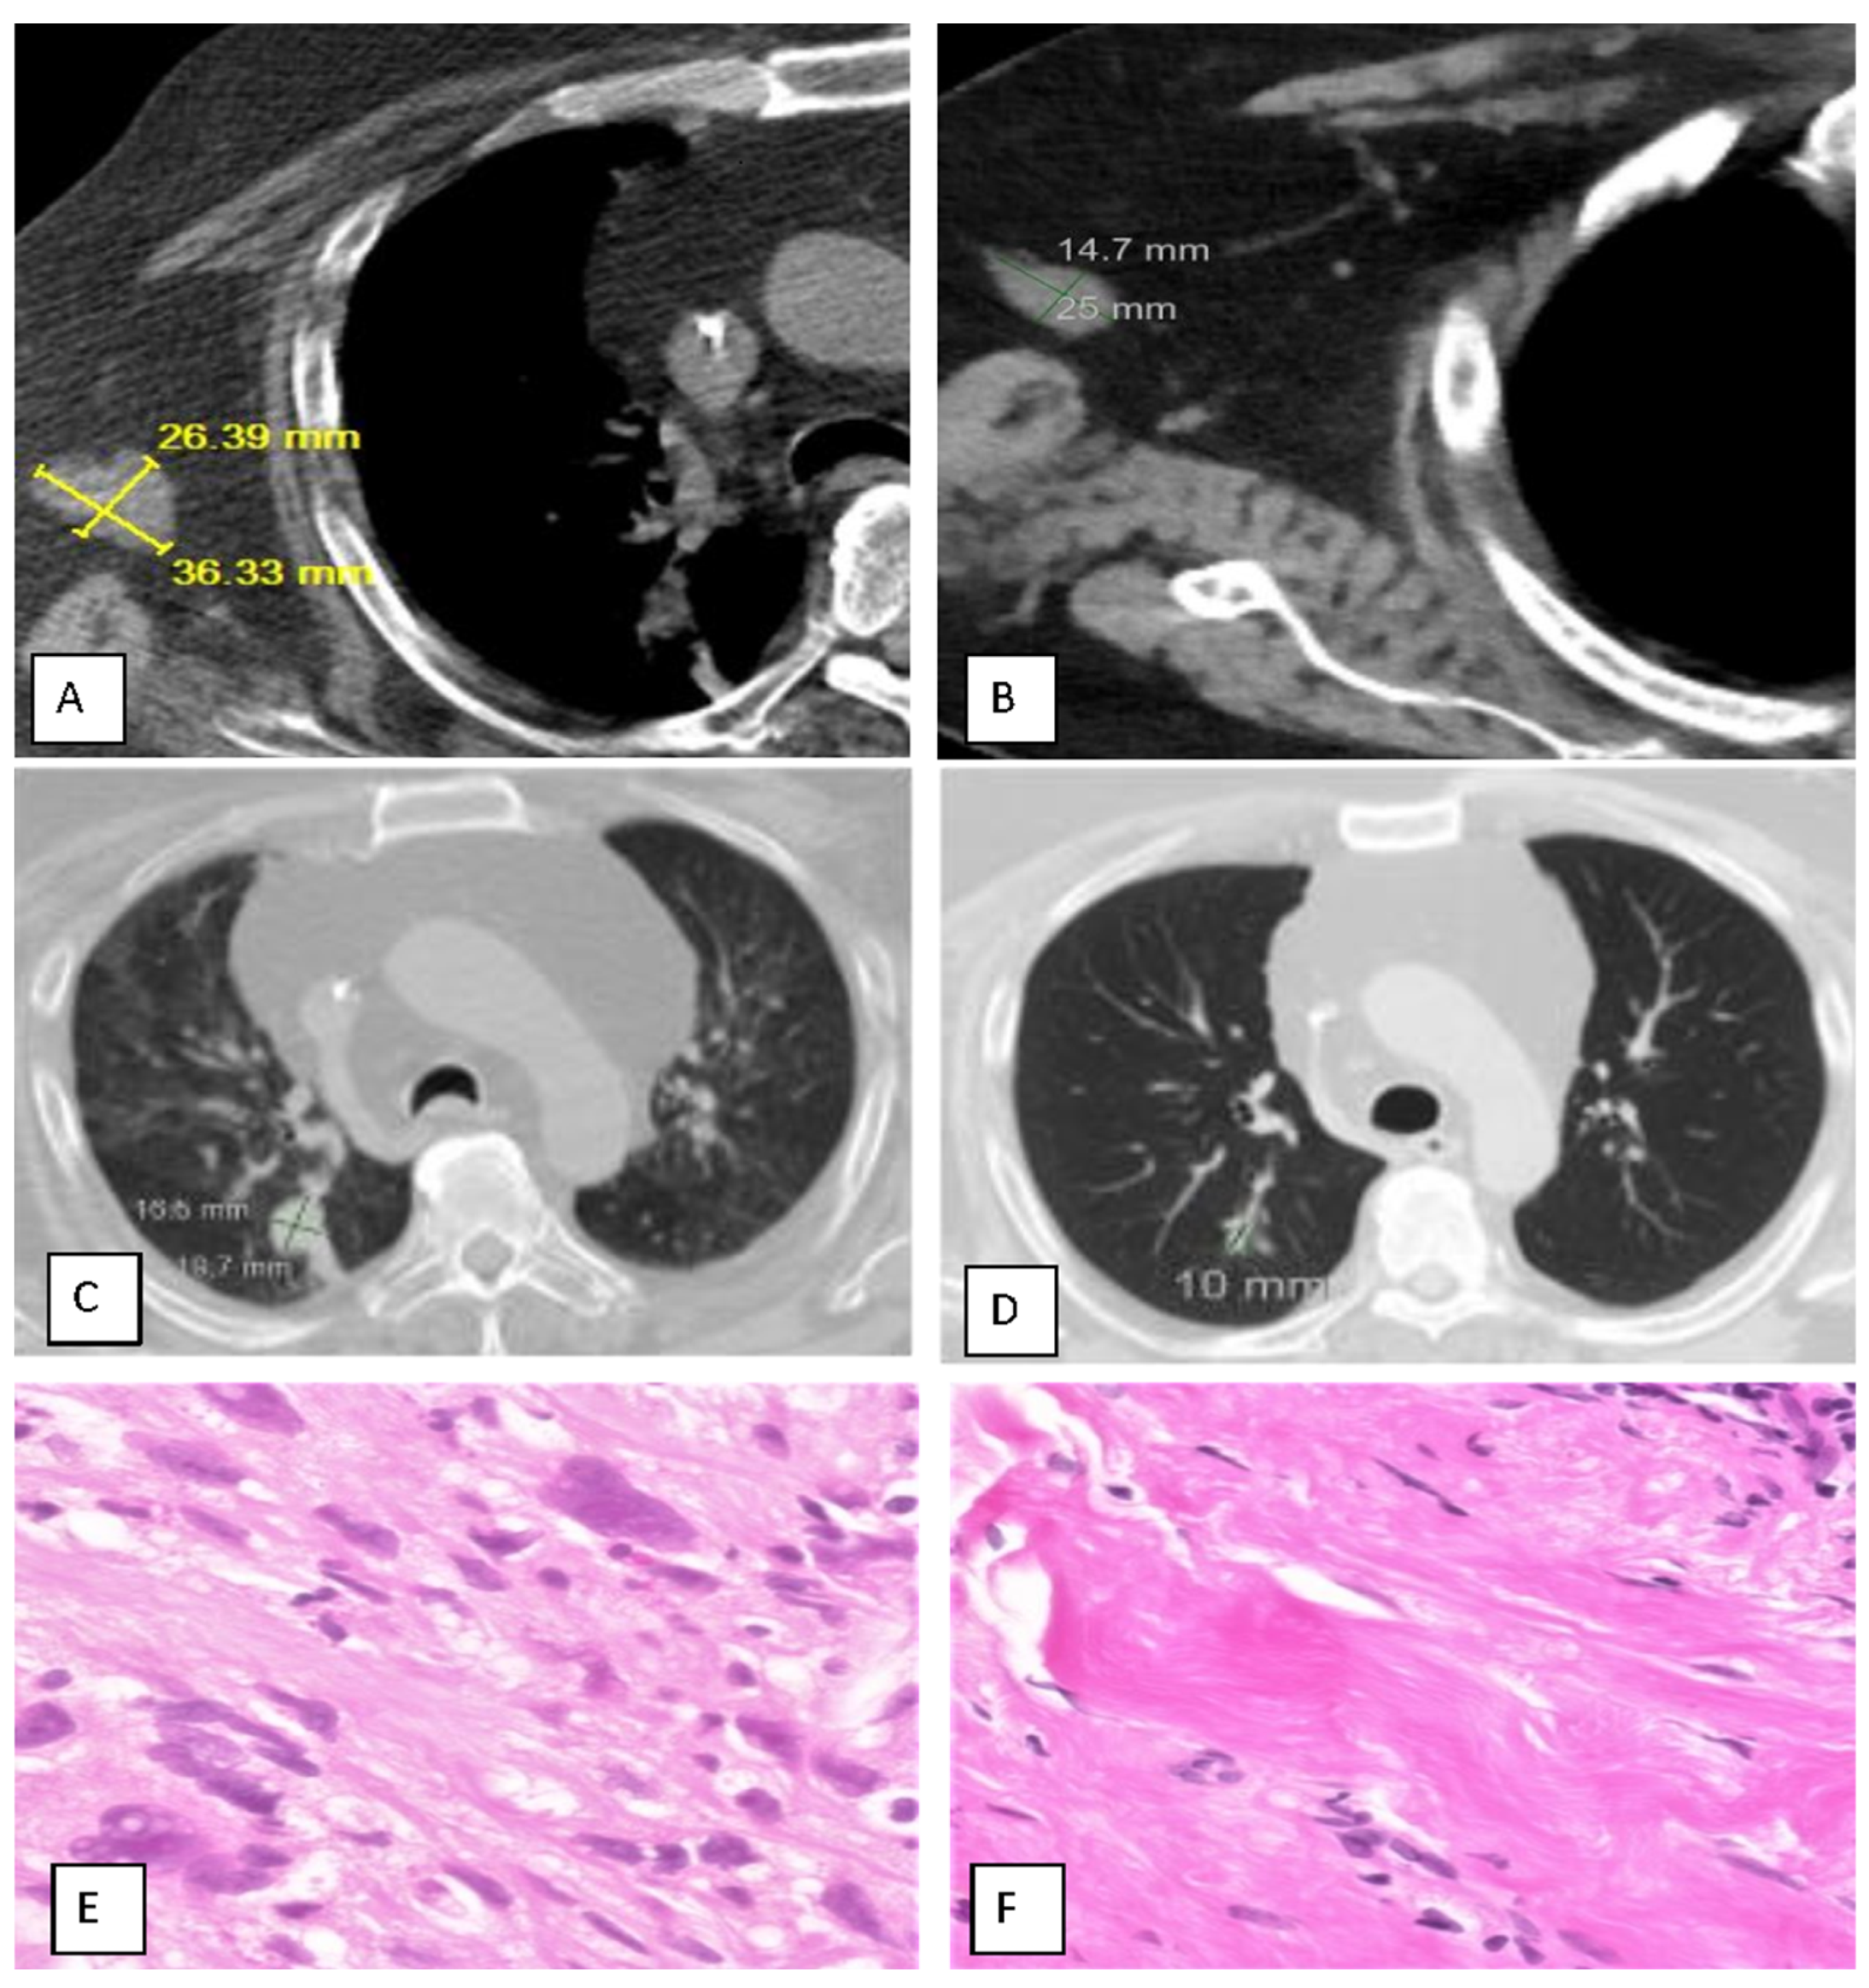

Upon completion of up to three cycles of treatment, complete response (iCR) was observed in 1 patient (7.7%), partial response (iPR) in 4 patients (30.8%), and stable disease (iSD) in 5 (38.5%), for a disease control rate (iDCR) of 77%; progression was observed in 23% (Table 2). The best response ranged from 0 to 91%, with a mean for responding patients of 38%. The injection site response was observed in nine (69%) patients, and a distal abscopal effect was seen in four (31%), including one sarcoma patient with a complete abscopal response of lung metastases (Figure 1) and one bladder cancer patient with resolution of lung and liver metastases.

An adult patient with a long history of myxoid fibrosarcoma (grade 4 of 4) required left arm above-the-elbow amputation and radiotherapy to the left rib in 2020; however, he was intolerant to chemotherapy. By 2021, he had widespread metastases, including right lung nodules, right axillary lymph nodes, soft tissues of the left arm (stump), and a recurrent left rib. He underwent two cycles of MITI, resulting in the resolution of all but rib metastases within 2 months. The only adverse event was transient injection site discomfort, which was treated with acetaminophen.

Figure 1. Case Study of a Patient Successfully Treated with MITI for Metastatic Fibrosarcoma. (A,C,E), Before treatment; (B,D,F), After treatment. CT SCAN: Left arm stump mass. (A): 36.3 × 26.4 mm = 958.2 mm2 (abnormal; all cancer); (B): 25 × 14.7 mm = 367 mm2 (substantial shrinkage; complete resolution of cancer according to biopsy (see (F), below)). CT SCAN: Lung, Right Lower Lobe mass. (C): 19.7 × 15.5 mm = 305.4 mm2 (abnormal); (D): 10 × 8 mm = 80 mm2 (normal) (substantial shrinkage; complete resolution of cancer); Biopsy Histopathology: Left Arm Stump. (E): Cancer: Myxoid Fibrosarcoma; (F): Benign Fibrous Pseudotumor.